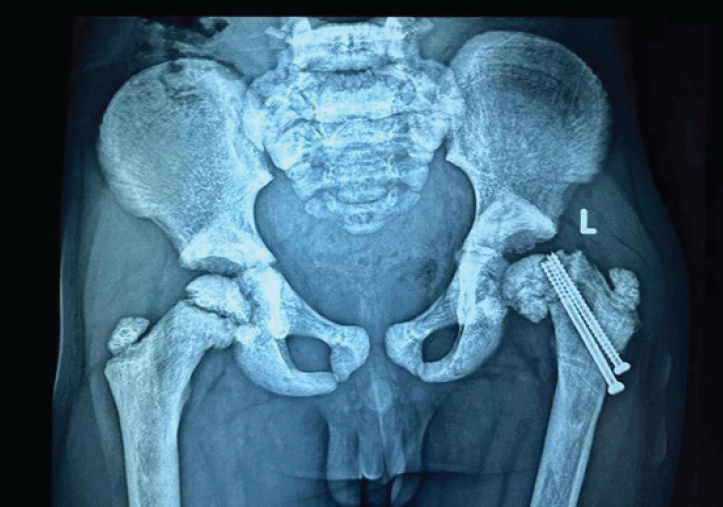

A 6-year-old boy presented to the emergency department with pain and inability to bear weight on the left lower limb following a trivial slip and fall. Clinical examination revealed restricted and painful movements of the left hip. Radiographs of the pelvis demonstrated a fracture of the left femoral neck with marked sclerosis of the pelvic bones and proximal femur, raising suspicion of a pathological fracture (Fig. 1).

Figure 1: Anteroposterior radiograph of pelvis with both hips at presentation showing left femoral neck fracture with diffuse bony sclerosis.

The patient underwent closed reduction on a fracture table using traction and internal rotation, followed by internal fixation with two 4-mm cannulated cancellous screws, deliberately stopping short of the physis (Fig. 2).

Figure 2: Immediate post-operative radiograph showing fixation with two cannulated cancellous screws (May 07, 2024).

Postoperatively, a hip spica cast was applied for 7 weeks. After removal of the hip spica cast, gradual physiotherapy and progressive weight-bearing were initiated under clinical supervision. Follow-up radiographs after cast removal showed satisfactory fracture healing (Fig. 3).

Figure 3: Radiograph at 7-Weeks follow-up after Hip Spica Cast removal showing progressing fracture union without evidence of avascular necrosis.

At 3 months, the fracture had united without evidence of avascular necrosis or non-union (Fig. 4), and the child had a painless full range of hip movements. Full weight-bearing ambulation was initiated.

Figure 4: Radiograph at 3-month follow-up showing progressing fracture union without evidence of avascular necrosis.

Seven months postoperatively, the child presented with a painless limp and apparent limb shortening. Radiographs revealed slippage of the capital femoral epiphysis despite fracture union (Fig. 5).

Figure 5: Radiograph at 7-month follow-up demonstrating slippage of the capital femoral epiphysis.

The likely cause was stress concentration at the screw tips adjacent to the physis. Revision fixation was deferred due to the small size of the epiphysis and anticipated poor screw purchase. At 1-year follow-up, radiographs demonstrated progression of epiphyseal slippage with significant limb length discrepancy (Fig. 6), although the child remained painless and ambulatory.

Figure 6: One-year post-operative radiograph showing progression of epiphyseal slip with limb length discrepancy.